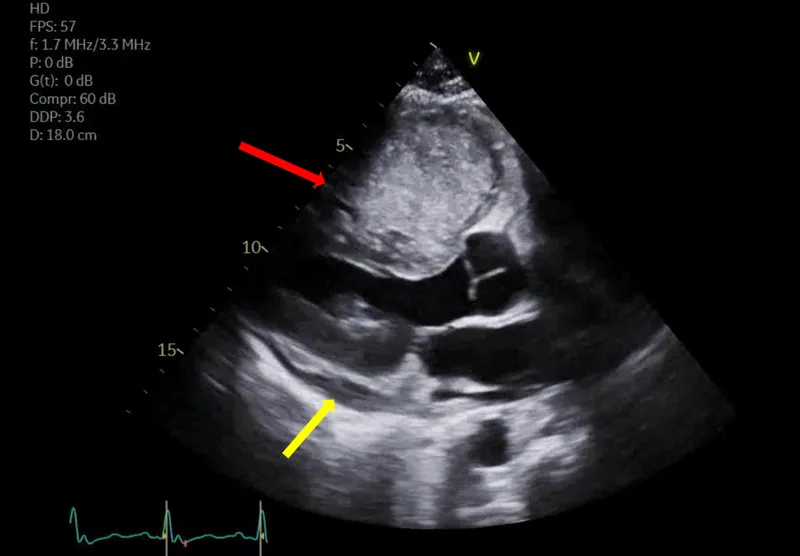

- Location: ~75% arise in the left atrium, often attached to the interatrial septum at the fossa ovalis.

- Obstructive: Mimics mitral stenosis (dyspnea, syncope). Positional symptoms are common. Auscultation may reveal a diastolic "tumor plop."

- Echocardiography (TTE/TEE) is the initial and primary diagnostic tool.